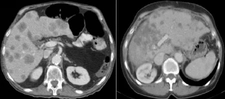

Böbrekte kistik lezyon, genellikle böbrek dokusunda sıvı dolu kesecikler (kistler) oluşturan, benign (iyi huylu) ya da malign (kötü huylu) olabilen yapılar olarak tanımlanabilir. Bu lezyonlar, böbreklerin normal işlevlerini etkileyebilir ve bazı durumlarda belirti vermeden uzun süre varlık gösterebilirler. Kistik lezyonlar, genellikle görüntüleme yöntemleriyle (ultrason, bilgisayarlı tomografi, manyetik rezonans görüntüleme) tespit edilir. Kistik Lezyonların TürleriBöbreklerdeki kistik lezyonlar, birkaç farklı türde sınıflandırılabilir:

Tanı ve Teşhis YöntemleriKistik lezyonların tanısı, çeşitli görüntüleme yöntemleri ile konulmaktadır:

I. sağ böbrek üst polde 35x30 mm ebatlarında egzofıtık yerleşi̇mli̇ düzgün konturlu ki̇sti̇k kompenent i̇çeren soli̇d lezyon mevcuttur.( kontraslı tüm batın bt öneri̇li̇r. ) raporu yorumlayabilir misiniz?

Rapor, sağ böbrek üst pole yerleşmiş bir lezyonu tanımlamaktadır. Bu lezyonun boyutları 35x30 mm olarak belirtilmiş ve düzgün konturlu olduğu ifade edilmiştir. Düzgün konturlu lezyonlar genellikle iyi huylu yapılarla ilişkilendirilir, ancak kesin bir değerlendirme için ek tetkiklere ihtiyaç vardır.

Egzofitk yerleşim, lezyonun böbreğin dışına doğru büyüdüğünü göstermektedir. Bu durum, lezyonun doğasına dair ipuçları verebilir. Solit lezyonlar, genellikle tek başına bulunan ve çevresinde yayılım göstermeyen oluşumlardır. Ancak, bu tür lezyonların değerlendirilmesinde görüntüleme yöntemlerinin önemi büyüktür.

Rapor, kontrastlı tüm batın BT (Bilgisayarlı Tomografi) önerilmektedir. Bu tetkik, lezyonun özelliklerini daha ayrıntılı incelemek, çevresindeki dokularla olan ilişkisini değerlendirmek ve olası metastaz veya yayılım durumunu gözlemlemek açısından büyük önem taşımaktadır.